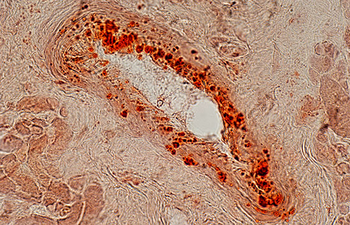

- Investigation of cell placement on tissue scaffold

- Cell transplant from blood as IP, sub-kidney and muscle capsule

- Tracking of transplanted cells